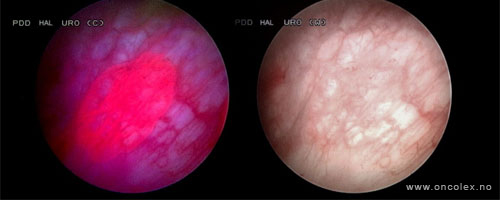

Bildeeksempler

Ved bruk av dette middelet i kombinasjon med et blått lys på cystoskopet, vil forandringer i urotelet vises i form av endret fargestruktur. Svulster vil da lyse rødt. Denne undersøkelsen betegnes fotodynamisk diagnostikk (PDD). Ved hjelp av denne metoden kan flere svulster oppdages på et tidlig tidspunkt sammenliknet med tradisjonell cystoskopi med hvitt lys alene.